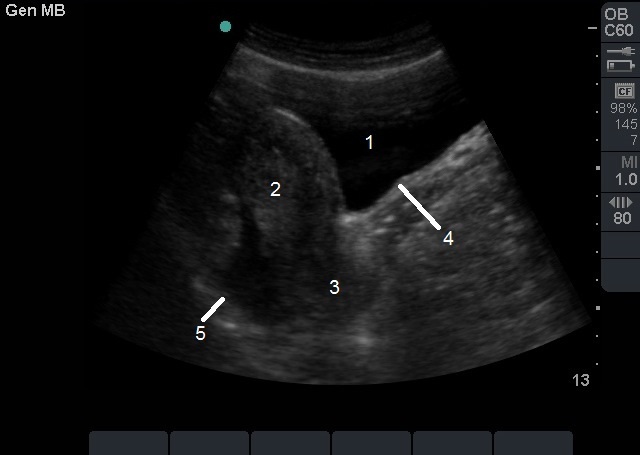

Pelvic Transabdominal (TA) Ectopic Free Fluid Image

1. Bladder

2. Empty Uterus

3. Cervix

4. Vaginal Stripe

5. Free Fluid in Posterior Cul-de-sac